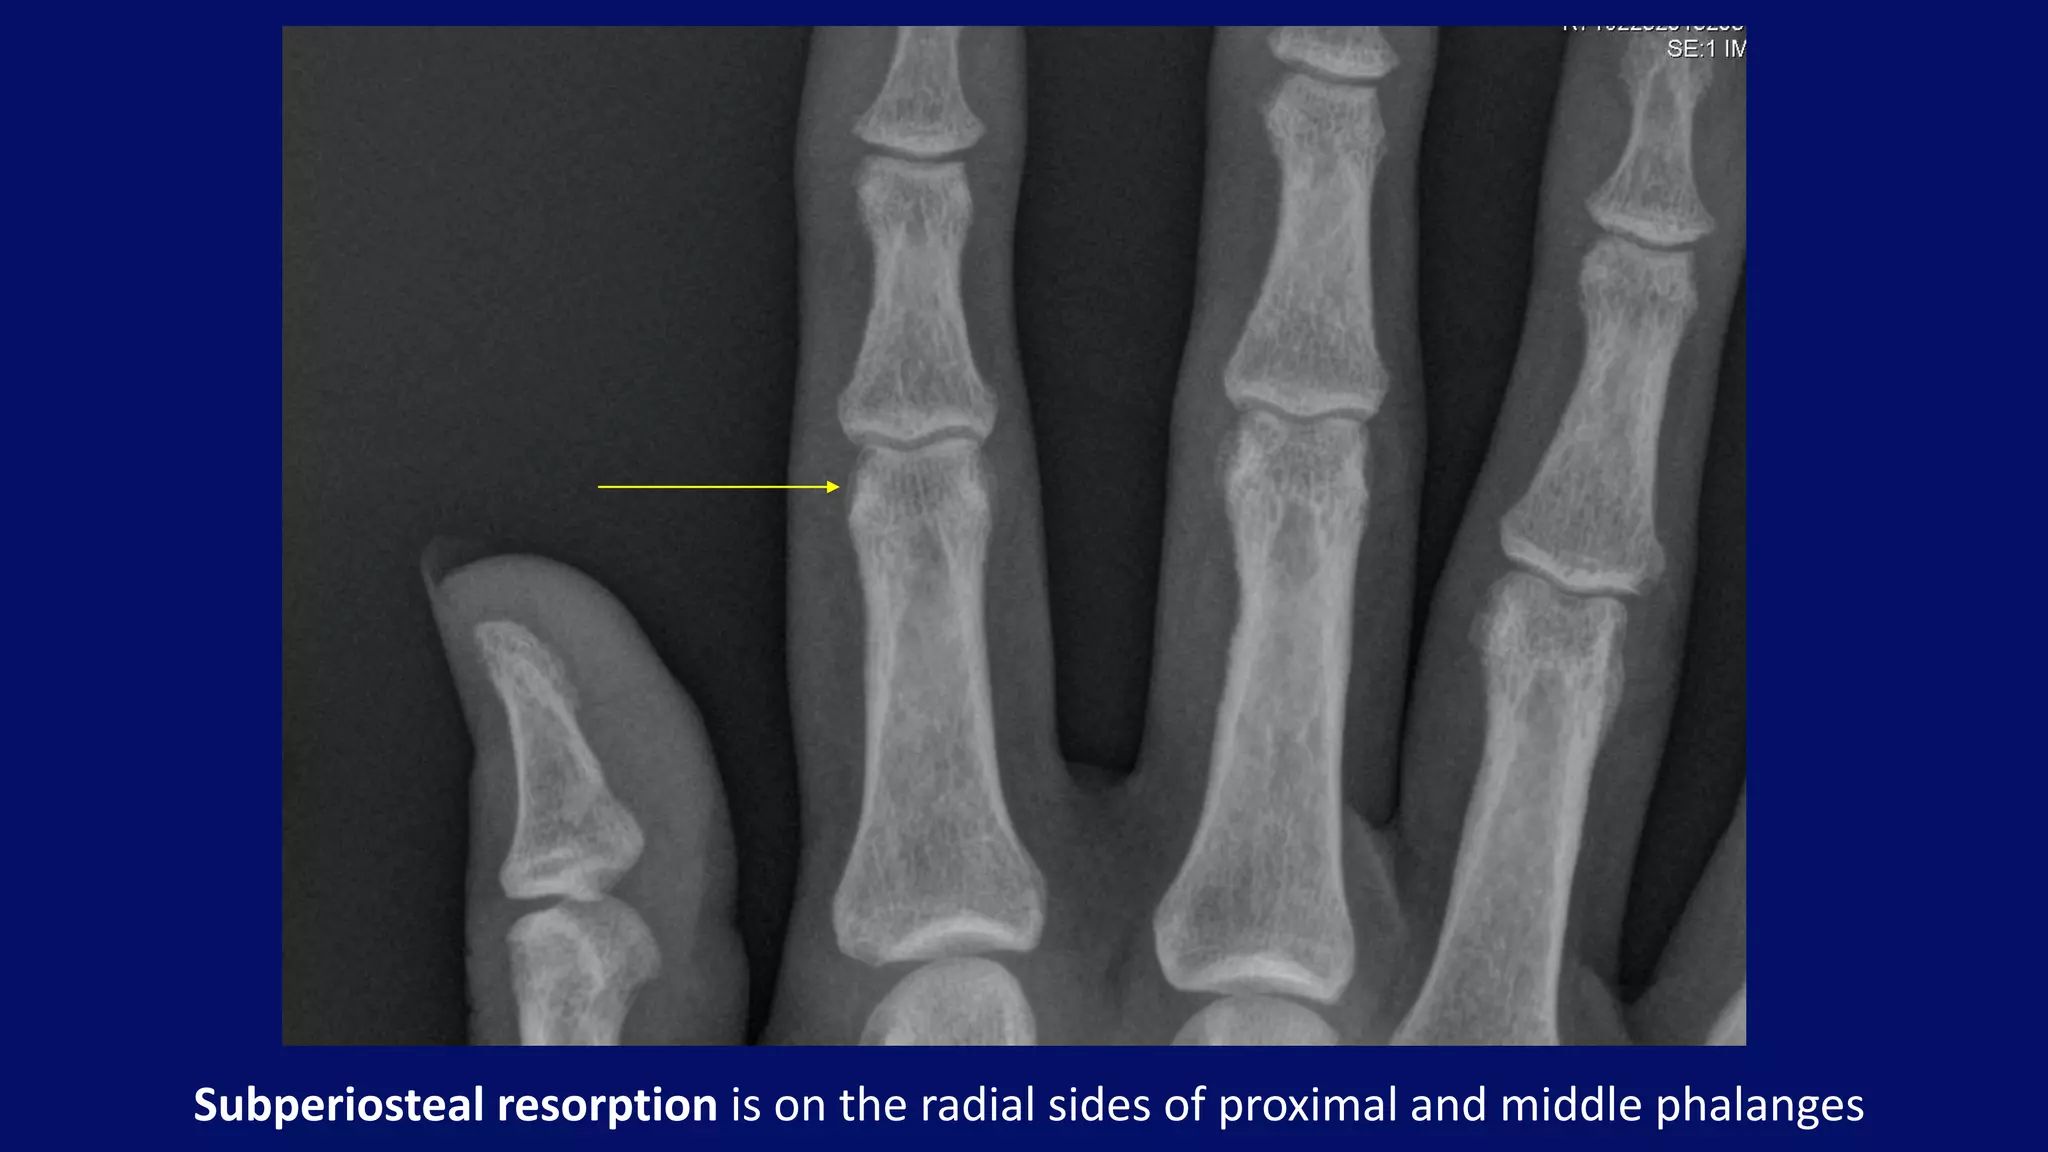

Subperiosteal resorption is on the radial sides of proximal and middle phalanges

• #100 subperiosteal bone resorption - classically affects the radial aspects of the proximal and middle phalanges of the 2nd and 3rd fingers

• #101 subperiosteal resorption Thirty year-old patient with chronic renal failure and elevated parathyroid hormone. Subperiosteal resorption is most evident on the radial sides of proximal and middle phalanges. Note the shaggy outer cortical surface in the mid-to-distal shaft of the middle finger proximal phalanx.